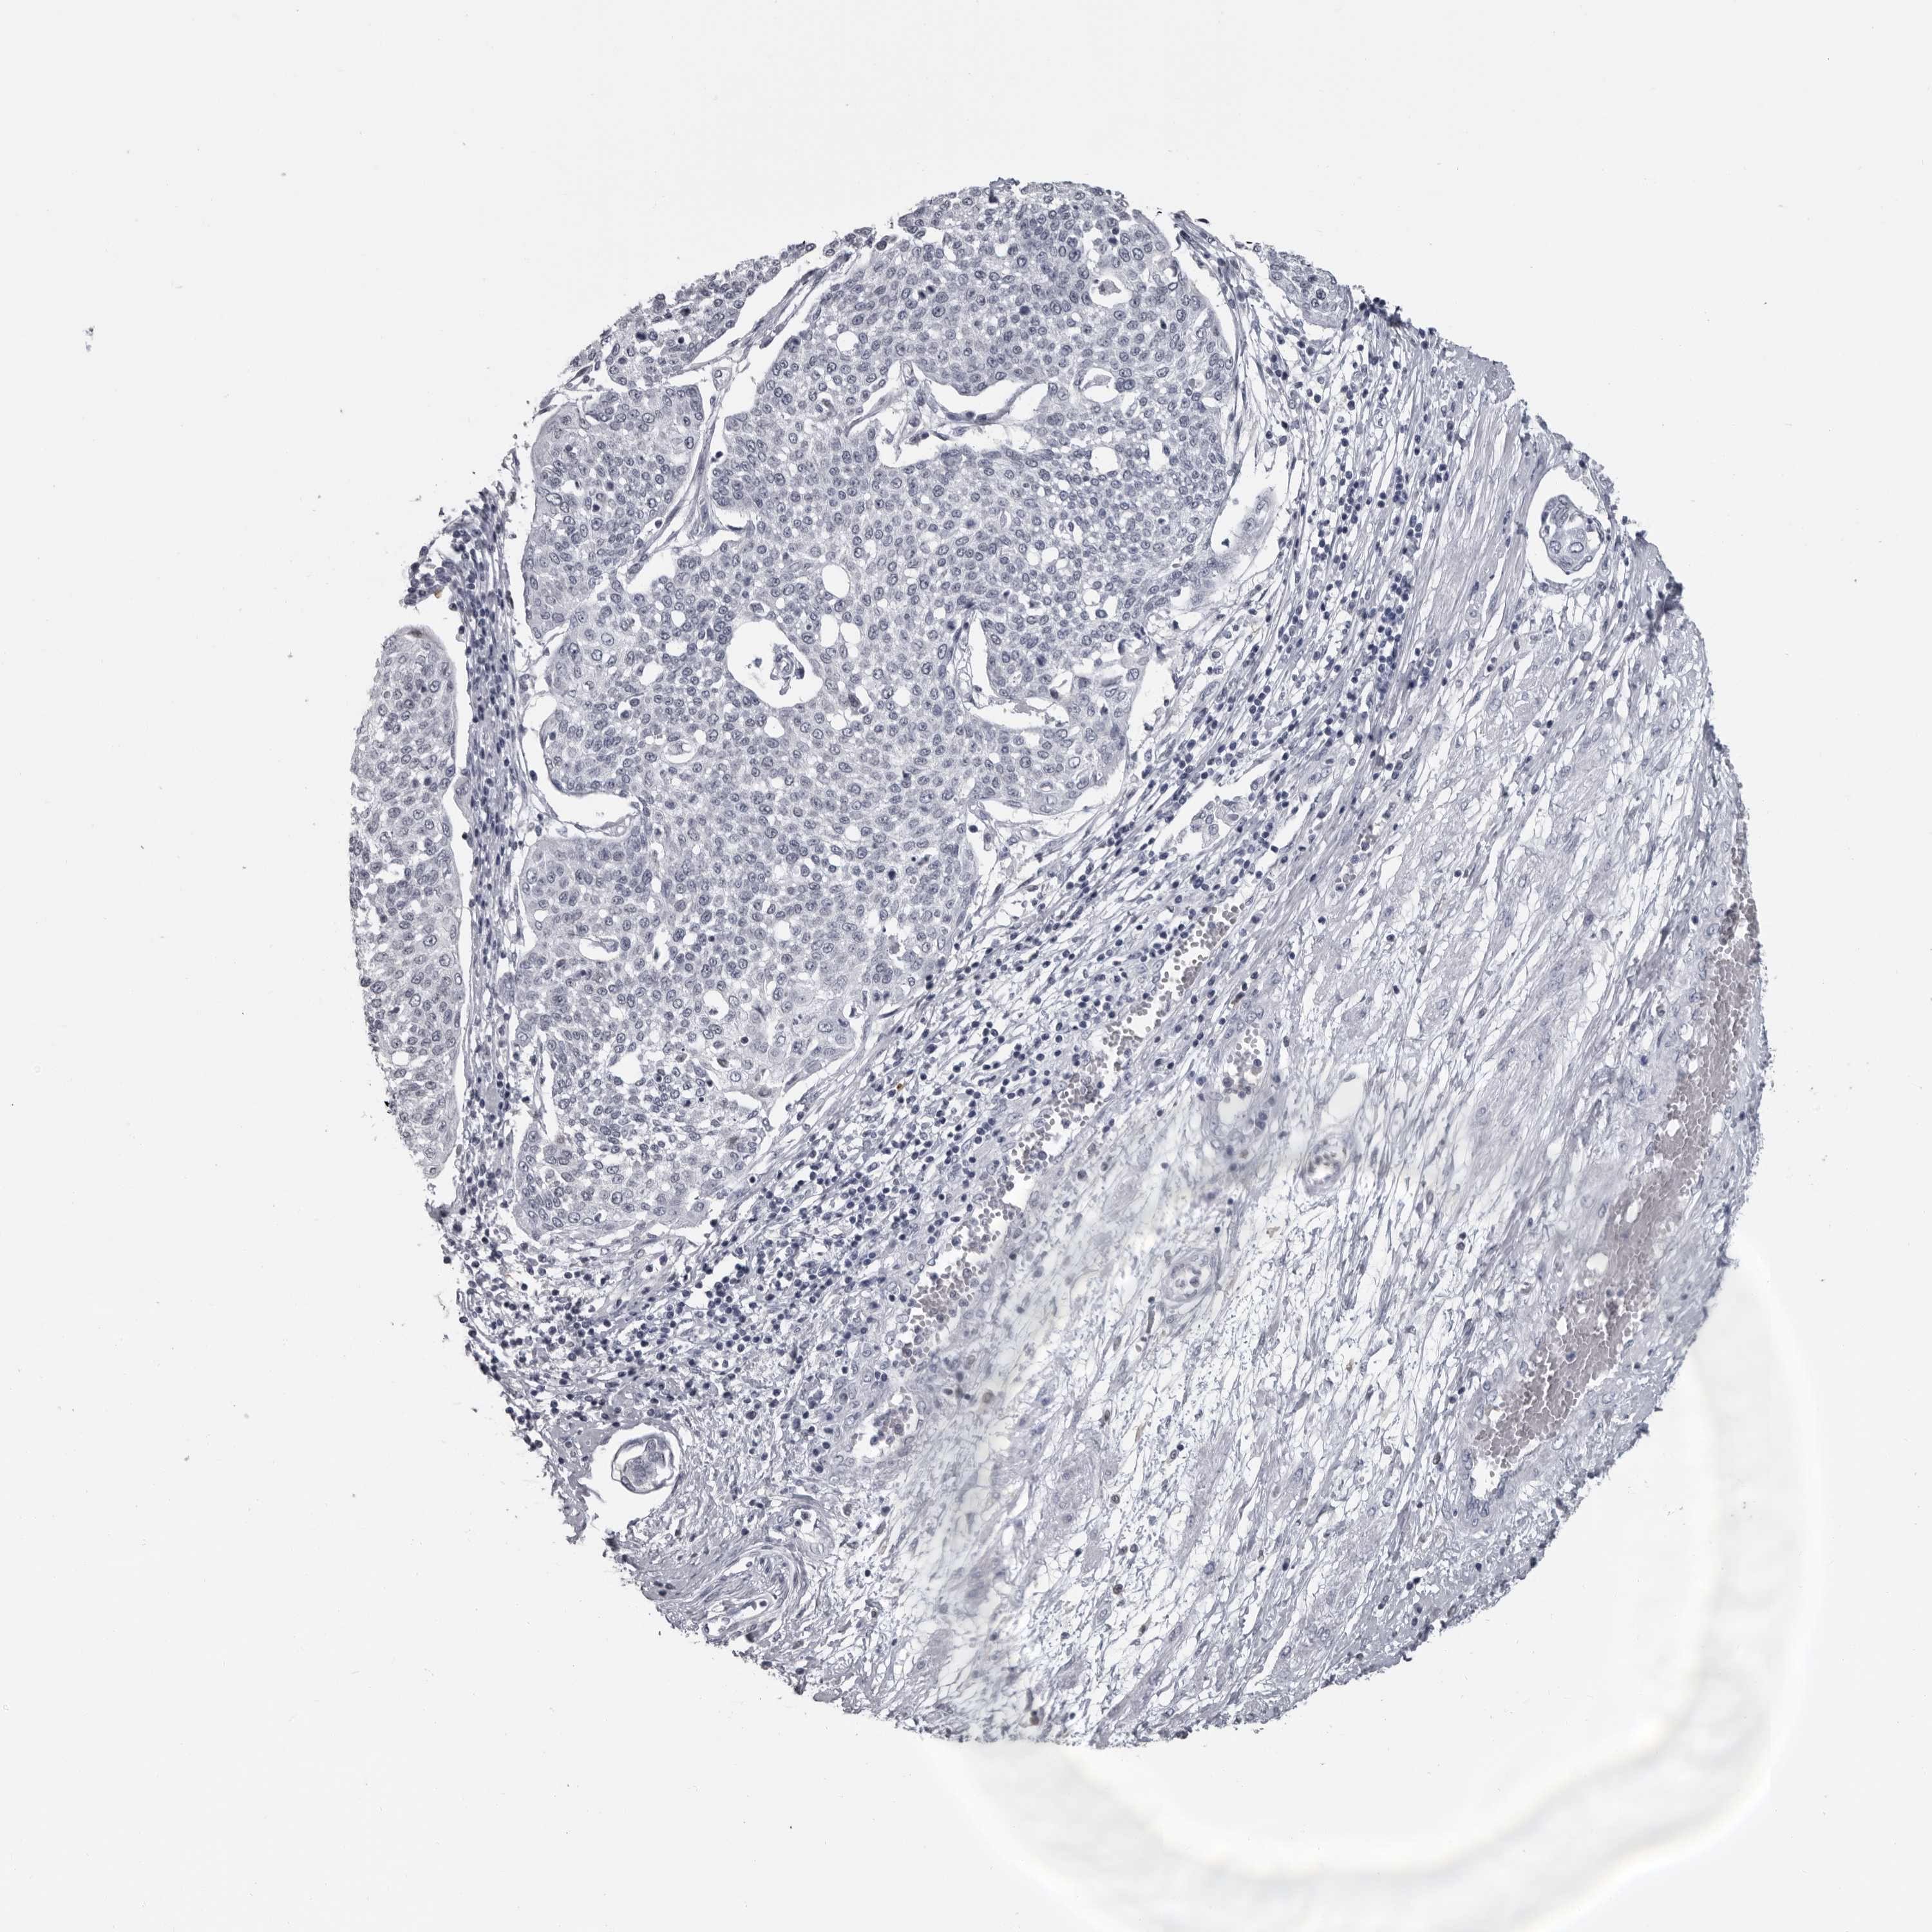

CERVICAL CANCER - Protein expressioni

A mouse-over function shows sample information and annotation data. Click on an image to view it in a full screen mode. Samples can be filtered based on level of antibody staining by selecting one or several of the following categories: high, medium, low and not detected. The assay and annotation is described here.

Note that samples used for immunohistochemistry by the Human Protein Atlas do not correspond to samples in the TCGA dataset.

Antibody stainingi

Antibody staining in the annotated cell types in the current human tissue is reported as not detected, low, medium, or high, based on conventional immunohistochemistry profiling in selected tissues. This score is based on the combination of the staining intensity and fraction of stained cells.

Each image is clickable and will lead to virtual microscopy that enables deeper exploration of all samples and also displays staining intensity scores, fraction scores and subcellular localization as well as patient and tissue information for each sample.

Antibody HPA028184

Staining

High

Medium

Low

Not detected

Intensity

Strong

Moderate

Weak

Negative

Quantity

>75%

75%-25%

<25%

None

Location

Nuclear

Cytoplasmic/membranous

Cytoplasmic/membranous,nuclear

Squamous cell carcinoma, NOS

Adenocarcinoma, NOS